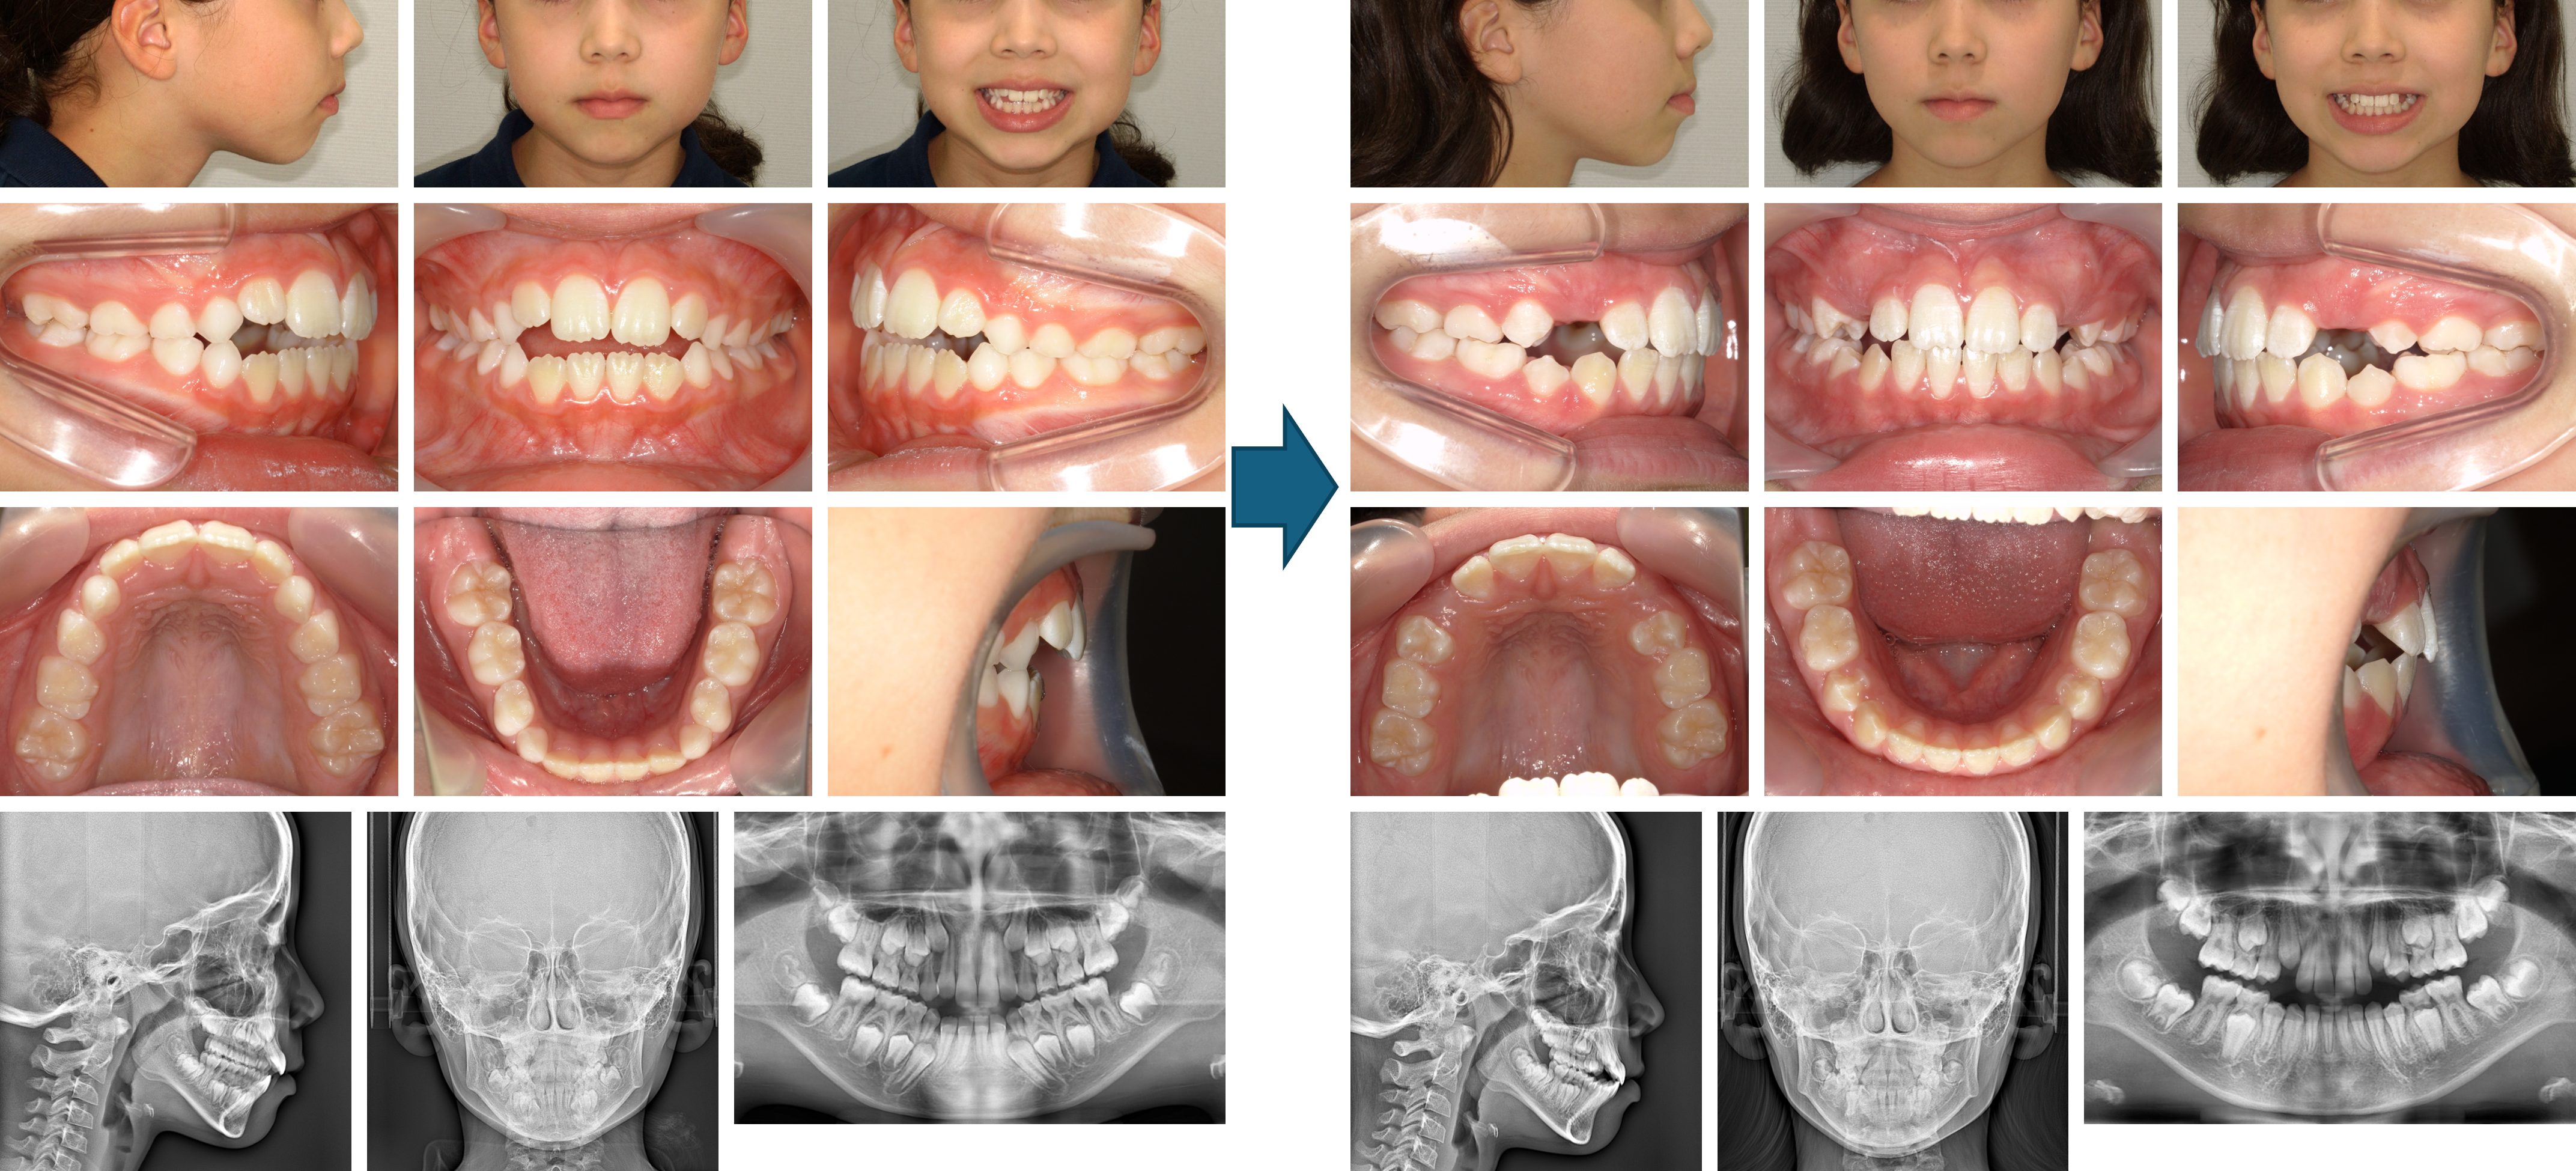

【治療例 K8146】初診時年齢:12歳4か月 / 性別:女性 / 主訴:出っ歯、口が閉じにくい

症例の概要:前歯の出っ歯と口の閉じにくさを主訴に来院。アレルギー性鼻炎により、就寝時も口が開いていることが多いとのことであった。マウスピース型(アライナー型)矯正装置(インビザライン®)を用いてIPRを併用し、非抜歯で治療を行った症例である。治療後の側貌では口元の突出感の改善が認められた。

主訴:出っ歯、口が閉じにくい

診断名:口唇閉鎖不全を伴う上顎前突症例

使用した主な装置:マウスピース型(アライナー型)矯正装置(インビザライン®)、IPR

抜歯/非抜歯および抜歯部位:非抜歯

治療期間:1年6か月

治療回数:21回

アライナー枚数:初回51枚(30枚で中止)+追加①22枚+追加②9枚 合計61枚使用